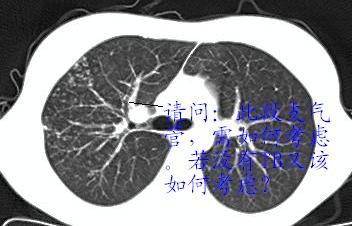

以下是引用x线在2006-2-2 17:37:00的发言:[br]结合病史支持“ct拟诊:双侧tb,左下叶结核球,左下叶局限性轻度支扩。”双下叶及左舌叶淡薄的毛玻璃密度影,我考虑为炎性渗出。另:是否合并霉菌感染须进一步检查确定。